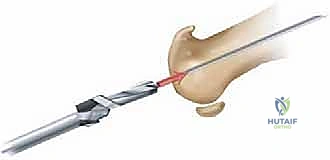

- ما هي؟ جراحة يتم فيها "تنظيف" المفصل. يقوم الجراح بإزالة النتوءات العظمية (Bone Spurs) من أعلى المفصل، بالإضافة إلى إزالة جزء صغير من أعلى رأس عظمة المشط.

- الهدف: إزالة العائق الميكانيكي الذي يمنع حركة الإبهام لأعلى، مما يخفف الألم ويحسن نطاق الحركة.

- ما هي؟ الإجراء "الذهبي التقليدي" لتخفيف الألم. يتم إزالة الغضروف المتبقي، وتثبيت عظام المفصل معاً باستخدام مسامير أو شرائح معدنية حتى تلتحم العظام وتصبح عظمة واحدة صلبة.

- ما هي؟ استبدال أسطح المفصل التالفة بمواد صناعية. وهنا تبرز التقنية الأحدث والأكثر نجاحاً عالمياً: **تقنية Arthrosurface